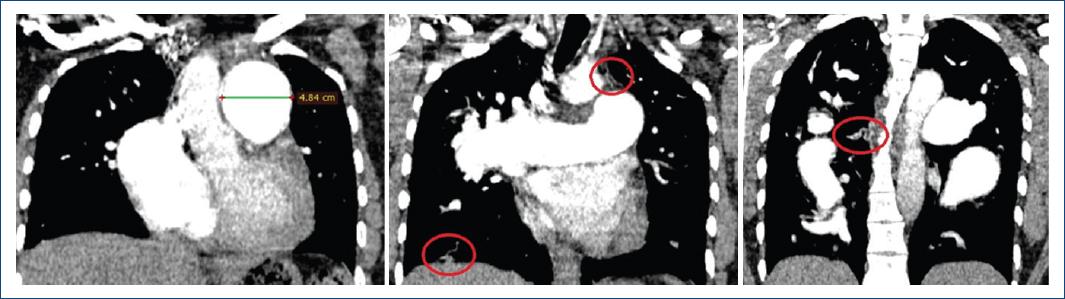

We present the case of a 35-year-old patient with neurological maturation retardation and a history of bicuspid aortic valve and subaortic membrane, who had started 15 days earlier with progressive dyspnea of functional class II to III-IV, orthopnea and angina in the last 24 hours. She had edema in the lower limbs, crackles in the lung bases, first and second tones present, and a tricuspid systolic murmur of 3/6 intensity with Rivero Carvallo's sign. The chest X-ray revealed cardiomegaly and dilatation of the pulmonary artery (Figure 1). Transthoracic echocardiography showed a preserved ejection fraction, systolic flattening of the interventricular septum, slightly dilated right ventricle with a 19 mm TAPSE, bicuspid aortic valve with preserved opening, with a small subaortic membrane, pulmonary, tricuspid, mitral and mild aortic aortic insufficiencies, PSAP 67mmHg, without intracardiac shunts. Acute pulmonary embolism was excluded by pulmonary angiography. The tomography showed a dilation of all the branches of the pulmonary artery (Figures 2 and 3). The right heart catheterization showed a mean pulmonary pressure (PAPm) of 52 mmHg, pulmonary capillary pressure (PCP) 13mmHg, pulmonary vascular resistance (PVR) 6 wood units, and cardiac index of 3.53 liters/minute/m2. Diuretic treatment with furosemide generated clinical improvement. Sildenafil and bosentan were subsequently started.

Figure 3 Three coronal sections of the pulmonary angiography. 48mm pulmonary trunk; red circle shows neovascularization.

This case is classified as a severe pulmonary hypertension precapillary phenotype of group 1.4.4 associated with congenital heart disease. The great dilation of the pulmonary artery and its branches led us to present chest radiography and pulmonary angiography images.